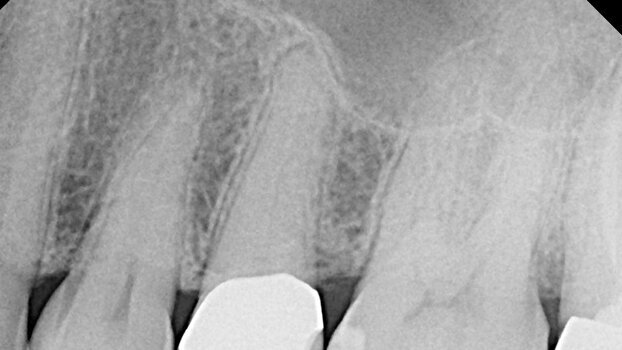

The patient pictured in Figure 1 was referred because the first clinician could not locate the canal(s). The patient had pain when chewing on #13 and mild spontaneous pain leading to a diagnosis of a non-vital pulp before referral. The referring doctor accessed the tooth without canal location. The patient was subsequently referred.

Upon referral the patient was asymptomatic and there was no swelling. The tooth was mildly percussion sensitive, and within normal limits to palpation, mobility and probings. Radiographic assessment of #13 showed open crown margins and calcified canals.